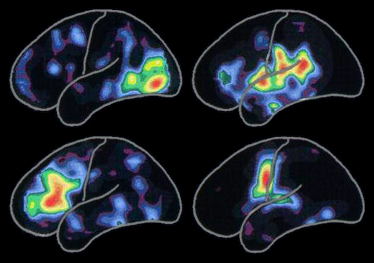

左圖所顯示的正電子放射X光攝影掃瞄(PET scan)顯示腦部做不同活動的模式:

紅色部份表示該區活動是最活躍的,次活躍區域依彩虹次序由黃色遞減到紫藍色。

一些特別的腦部活動模式會隨著生活而改變,例如認識新朋友、新體驗或學習新的技術。腦部活動模式亦會因為患上阿滋海默症或其他相關的腦疾病而改變。